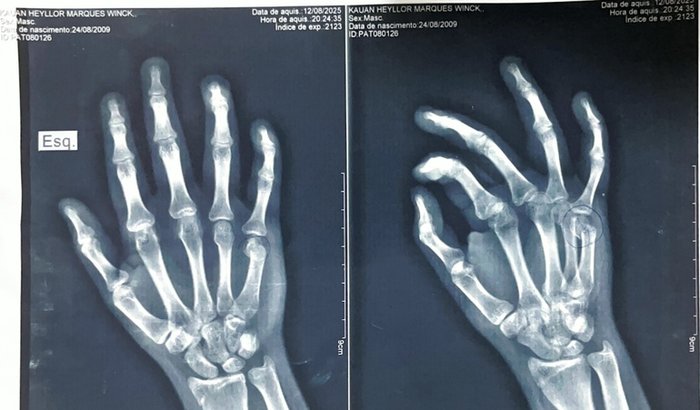

Eu sou a Adrielle e junto com a minha família criamos essa vaquinha em prol da cirurgia da mão do meu sobrinho Kauã. Um rapaz cheio de vida, de apenas 16 anos, sofreu um acidente doméstico causando a fratura de um osso crucial dos movimentos de sua mão esquerda.

O médico informou que deve ser feita a cirurgia de Osteossintese de 5º metacarpo com extrema urgência para ele não correr o risco de perder os movimentos da mão. O valor total da cirurgia ficou em R$8.790,00 mas devido as taxas do site, decidimos arredondar para R$$9.000,00.